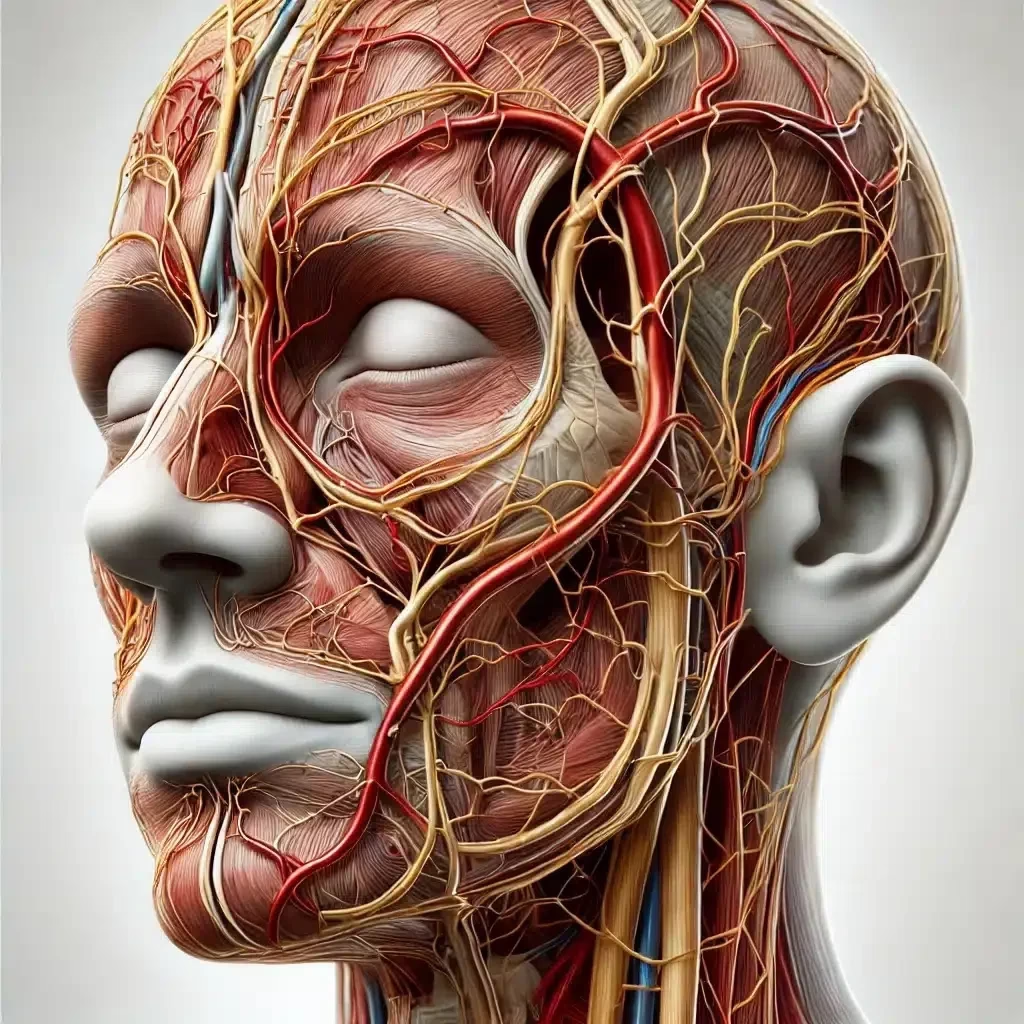

Forehead Vascular Occlusion by Dermal Fillers in the Glabella Area 101: A Comprehensive Clinical Review

Introduction Dermal filler injections have become a cornerstone of aesthetic medicine, providing a minimally invasive solution for rejuvenating facial features,…